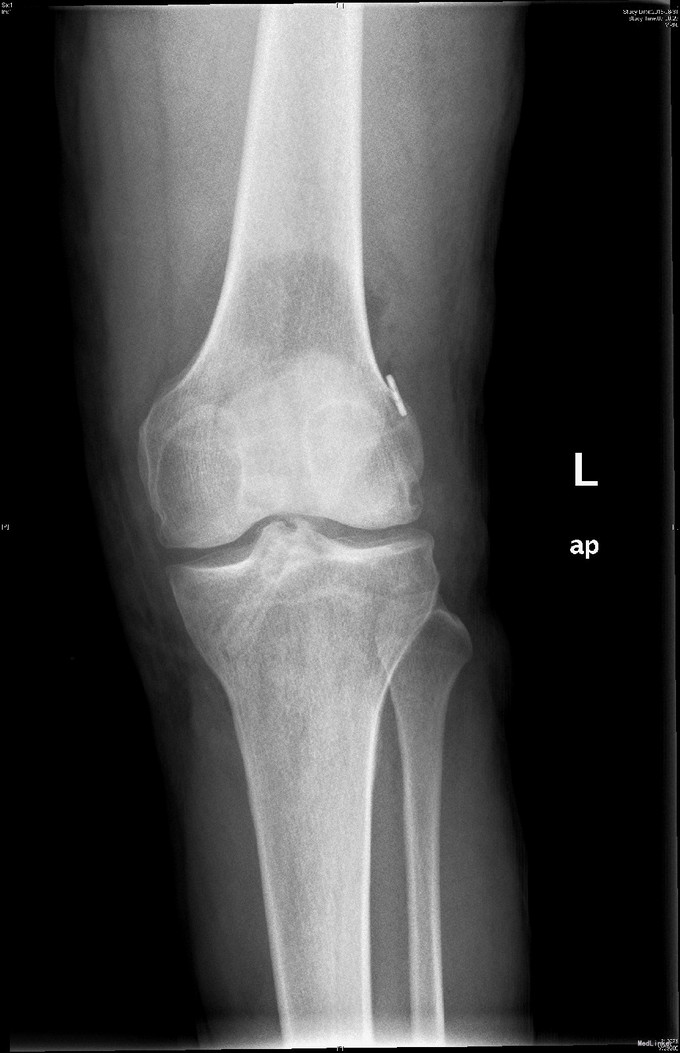

左膝扭伤后13年近1年反复不稳伴疼痛。 患者,男,39岁,13年前运动时扭伤左膝关节,当时未予重视,近1年出现左膝不稳伴疼痛,以上下楼、运动时明显,无法进行正常运动。遂于外院检查MRI(2015年3月)示:左膝关节退行性改变、左膝前交叉韧带信号异常、半月板信号异常、左膝关节内积液。为求进一步诊治来我门诊就诊,结合病史及体征,诊断“左膝半月板损伤、左膝前交叉韧带损伤”并收入院行进一步治疗。

右下肢、双上肢肌力及活动度正常。左股四头肌轻萎缩,肌力V-级。膝关节(无明显)肿胀,膝关节ROM受限:伸/屈:20度/110度,关节过伸过屈时无疼痛。髌骨活动度正常,髌周无压痛。浮髌试验(-),压、磨髌(+)。麦氏征(+),外侧关节间隙疼痛(+)。ADT(+),Lachman征(+),轴移试验(+),侧方应力试验(-)。双下肢无明显感觉异常。

入院诊断:左膝半月板损伤、左膝前交叉韧带损伤 治疗:入院后行左膝关节镜下外侧半月板成形+髁间窝成形+前交叉韧带自体肌腱重建手术。